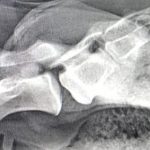

Seit wenigen Jahren bietet Next Generation Sequencing (NGS), ein Sammelbegriff für verschiedene Techniken der Hochdurchsatz-Sequenzierung, enorme Chancen zur breit angelegten Erregerdiagnostik. Allerdings ist NGS sowohl in Bezug auf technisches Know-how (labortechnisch, molekularbiologisch und bioinformatisch) als auch im Hinblick auf die Geräteausstattung eine herausfordernde Technik. Zur Implementierung müssen für verschiedene Probentypen (Serum, Stuhl, Nasenabstrich, Umweltprobe, …) zusätzlich jeweils individuelle Aufarbeitungsverfahren getestet und etabliert werden. Zur Evaluierung der Anwendungsmöglichkeiten von NGS in der Pockenvirusdiagnostik wurden im Rahmen dieser Arbeit beispielhaft Hautveränderungen eines Pferdes diagnostisch aufgearbeitet und ausgewertet. Die eingesetzten Methoden und Geräteplattformen wurden im Hinblick auf ihre Anwendbarkeit in der stationären und mobilen Diagnostik ausgewählt und verglichen. Der als ursächliches Agens identifizierte Erreger erwies sich als Vertreter einer neuen Virusspezies und wurde weitergehend charakterisiert.